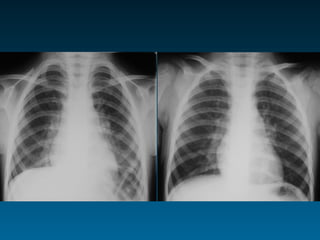

Αξία συγκριτικής αξιολόγησης

Διάμεσο πρότυπο